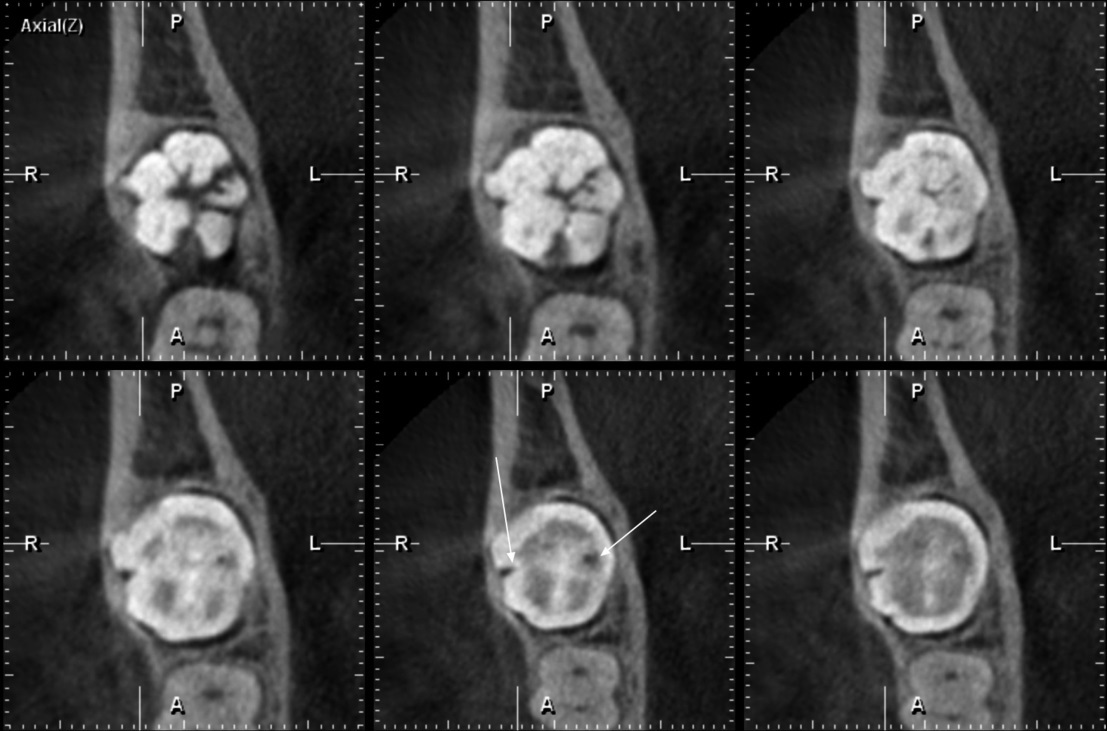

Se tiene la radiografía panorámica de una paciente femenina de 45 años de edad, en la que se observa un defecto de RIPE en la pieza impactada 48, de localización mesial y profundidad dentinal de grado I, y, además, un segundo defecto ubicado en el centro de la corona y de forma alargada, que sería consistente con una fosa vestibular (figura 8). En la THC adquirida, con un tamaño de vóxel de 0,2 mm, se observó que el aparente defecto de RIPE mesial era, en realidad, la fosa mesiobucal y, además, se encontró un defecto de RIPE, grado I, en la cúspide distolingual asociada a un defecto hipodenso del esmalte adyacente al defecto (figuras 9, 10 y 11).

En el caso 4, se observó la coexistencia de un defecto de RIPE y una fosa vestibular profunda. Hemos notado que las lesiones de RIPE tienen un mayor componente horizontal, mientras que la fosa vestibular profunda tiene un mayor componente vertical; tales diferencias podrían ser de utilidad al momento del diagnóstico diferencial.